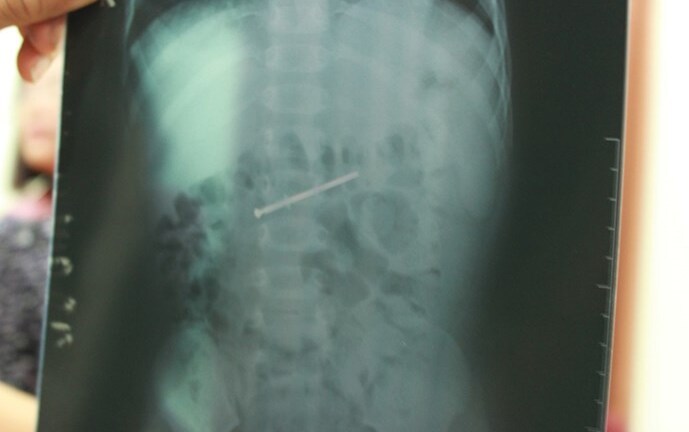

Trên hình ảnh phim X - quang các bác sĩ thấy một chiếc đinh cong, tiên lượng chưa xuyên thấu nhãn cầu nhưng dị vật này đã đâm xuyên giác mạc, qua mống mắc, xuyên qua thủy tinh thể làm đục vỡ thủy tinh thể.

Phim X-quang cho thấy vị trí chiếc đinh cắm sâu trong nhãn cầu bệnh nhân - Ảnh: VNexpress. |